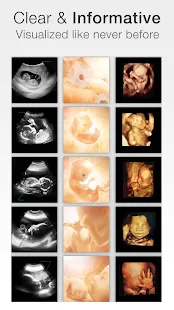

- Color and scan images

- More ultrasound images